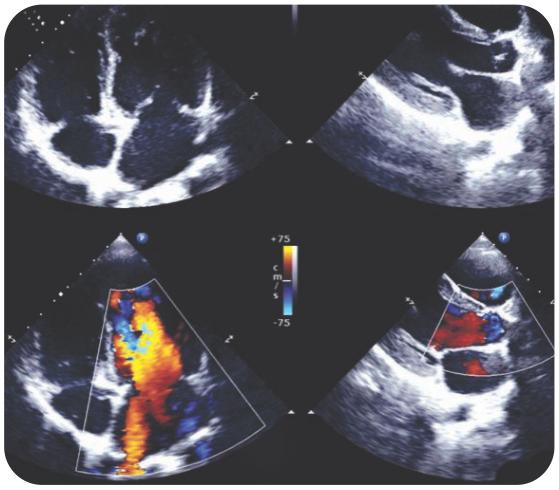

Case 7 - Acute Pulmonary Edema in Young, First Time Presented Severe Mitral Stenosis, Treated With BMV